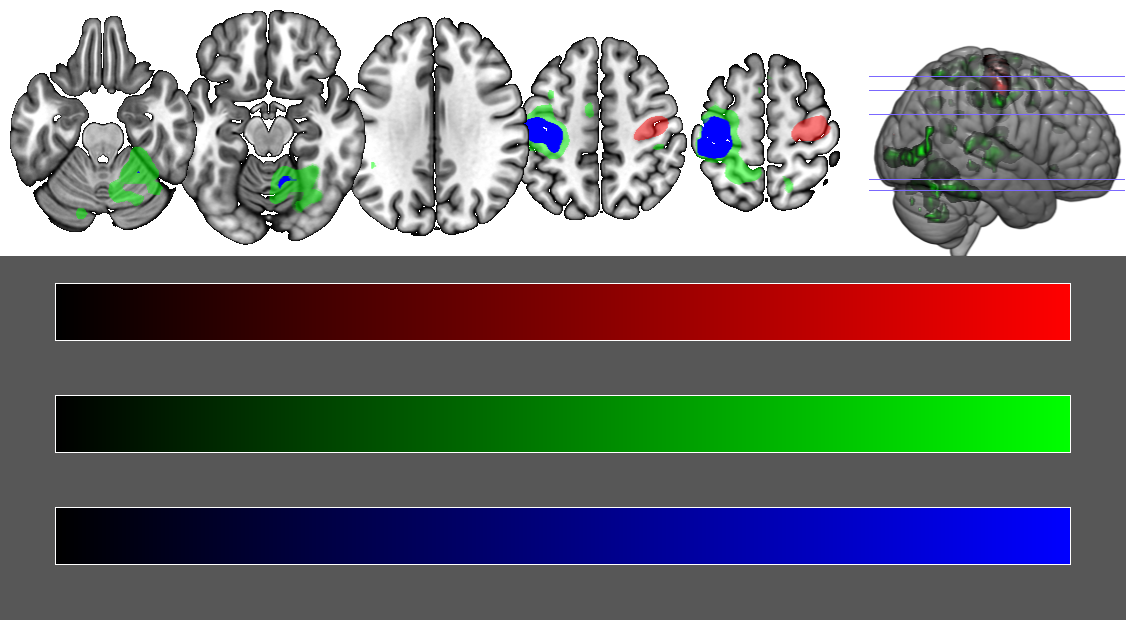

You will want to open the scripting window and use the function

overlaylayertransparencyonbackground()

the implementation of this function has changed a little bit, but the attached image is generated with v1.0.20180622 using this script